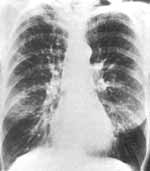

Развитие диффузной эмфиземы обусловливает низкое положение диафрагмы (Рис. 1) - ее уровень опускается до переднего конца 7-8-го ребра. Это более заметно у астеников и нормостеников, тогда как для лиц гиперстенической конституции типичнее увеличение передне-заднего размера грудной клетки. Еще показательнее уплощение диафрагмы, в особенности ее самой функционально значимой части - заднего ската. Реберно-диафрагмальные углы увеличены, подвижность диафрагмы ослаблена. При выраженной эмфиземе на вдохе становятся нередко видимыми зубцы в местах прикрепления диафрагмы к ребрам. При рентгеноскопии отчетливо уменьшена разница в площади легочных полей между вдохом и выдохом, и прозрачность их при дыхании меняется мало. Увеличение объема легких ведет к выстоянию кпереди грудины, к расширению более 3-4 см позадигрудинного пространства на боковой рентгенограмме, к увеличению межреберных

промежутков.

Рис. 1. Объяснения в тексте.